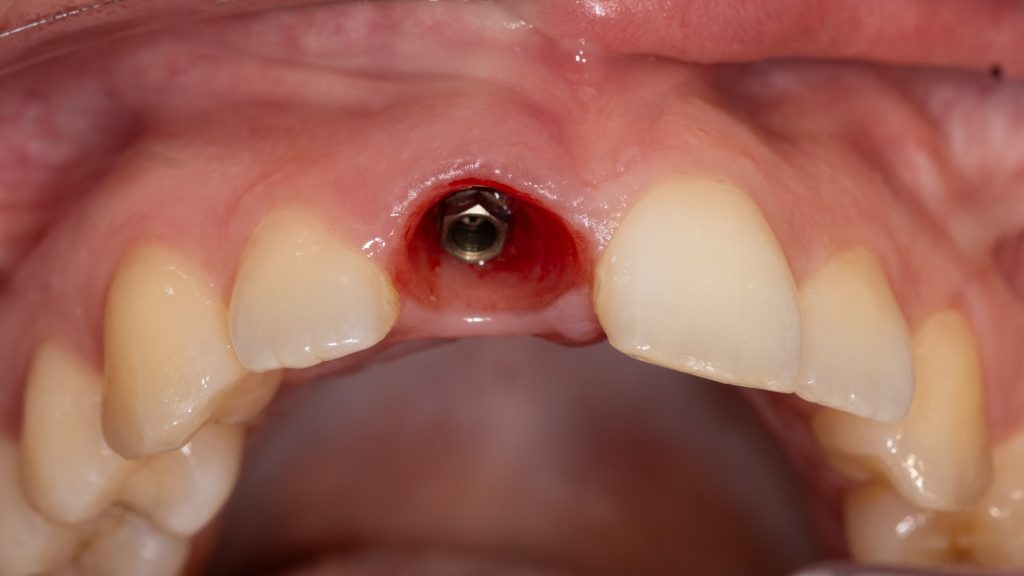

Surgical stage